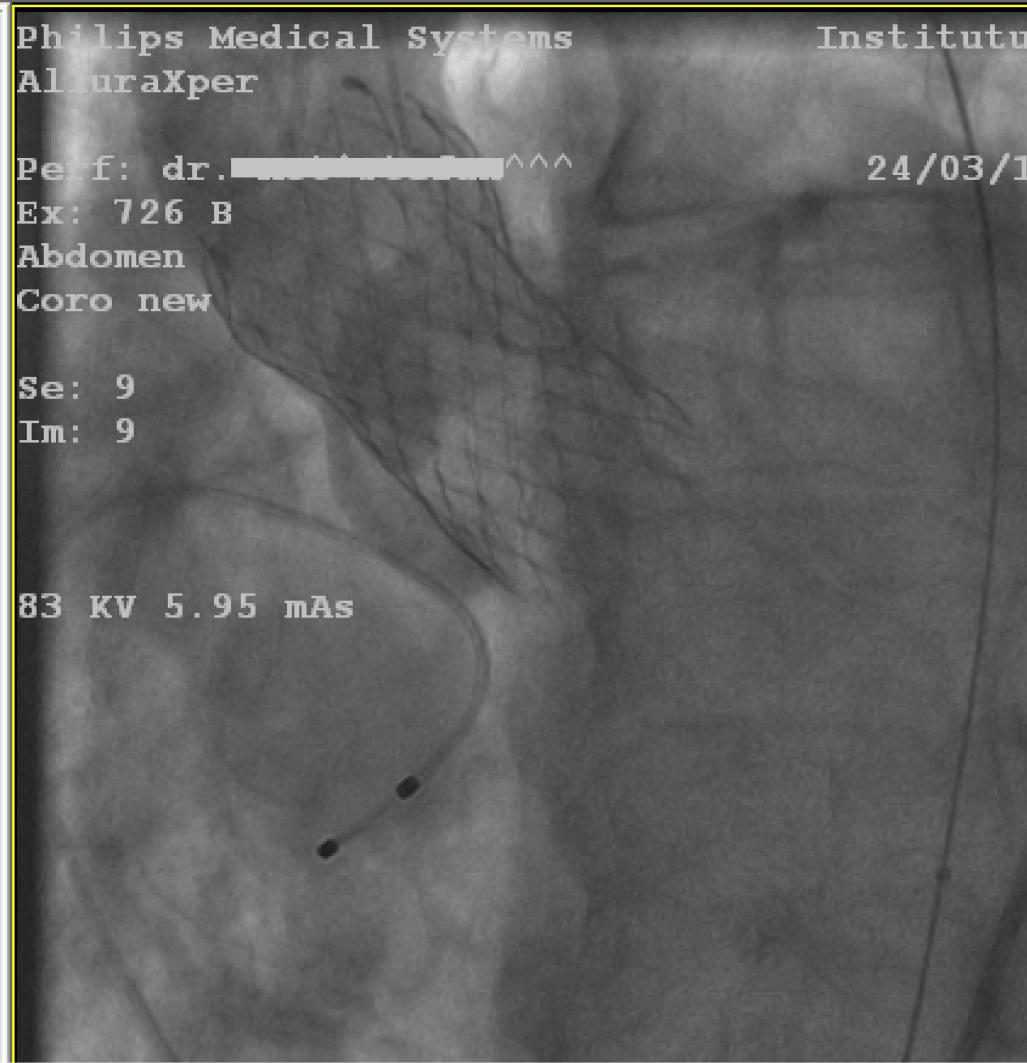

According to the European guidelines, aortic valve replacement should be considered before the the aortic aneurysmal repair. The patient was considered to be an intermediate risk candidate for surgical aortic valve replacement according to the EuroSCORE II (7%) and STS (8.2%) scoring systems, but given the association of patient’s frailty, advanced age (> 75 years), restricted mobility due to osteoporotic joint disease and the presence of a large abdominal aortic aneurysm, the Heart Team decided that the optimal treatment strategy for this patient is the transcatheter approach, TAVR followed by EVAR. The procedure was performed under spontaneous ventilation, with conscious sedation. A temporary pacing wire was inserted in the right ventricle, through the left common femoral vein to provide backup pacing in case of atrioventricular block development and rapid pacing for correct valve positioning. Bilateral percutaneous femoral access was obtained using the Seldinger technique, followed by pre-closure on both sides with two Proglide 6 Fr devices placed in a standard way. A 29 mm Medtronic Evolut R valve was inserted by an 18-French Sentrant Metronic sheath through the right femoral artery. After the direct deployment of the valve and balloon post-dilation under rapid pacing, the valve was correctly positioned and expanded (Figure 1), with a minor aortic insufficiency due to a paravalvular leak.

Fluoroscopic image: deployment of the Medtronic valve.